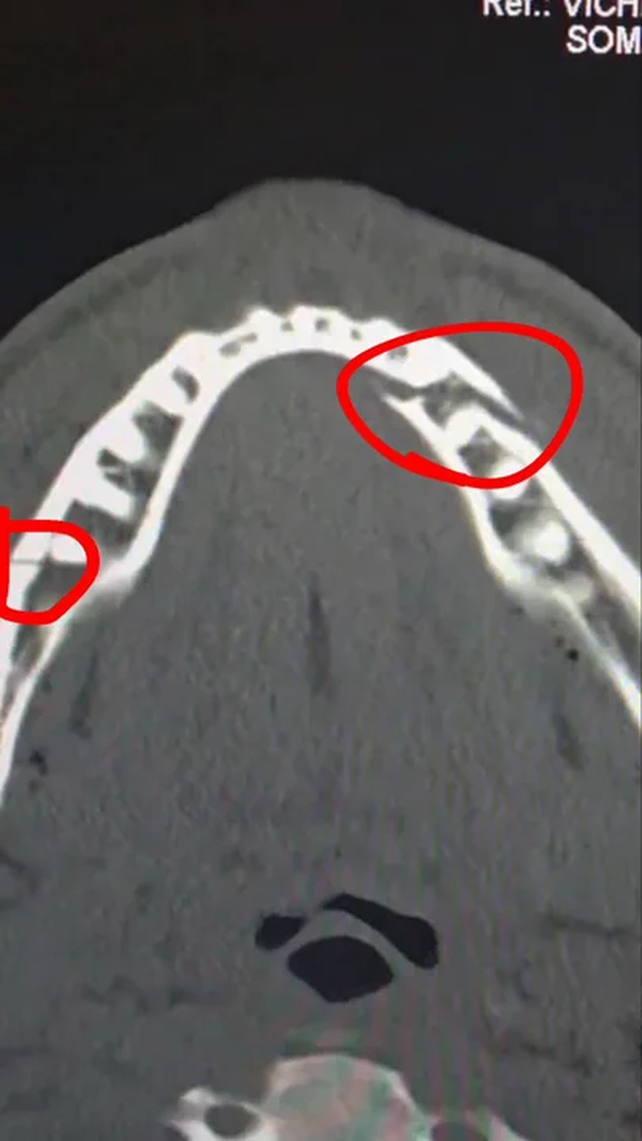

Paul, por su parte, compartió información en sus redes sociales sobre su estado de salud: “Mandíbula rota. Corazón y huevos intactos. Hora de descansar, recuperarse y volver al peso crucero”.

Luego posteó una imagen de la radiografía de su mandíbula, donde se observan las fuertes lesiones que produjeron los golpes de Joshua: “Doble rotura de mandíbula. Dame a Canelo en 10 días”.